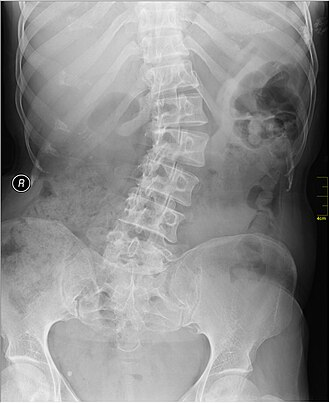

A escoliose é uma curvatura anormal da coluna vertebral no plano lateral. Em vez de seguir uma linha reta quando vista de frente ou de costas, a coluna apresenta uma inclinação para a direita, para a esquerda ou em ambas as direções.

Essa alteração pode ser leve, moderada ou grave, dependendo do ângulo da curvatura, que é medido por um exame chamado radiografia da coluna total, através do ângulo de Cobb.

O diagnóstico da escoliose é feito com base no exame físico e confirmado por radiografia panorâmica da coluna vertebral. Em alguns casos, exames complementares como ressonância magnética podem ser solicitados para investigar a causa da curvatura ou avaliar o grau de comprometimento neurológico.